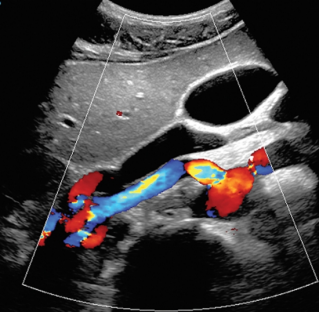

A national healthcare system that, for generations, has been focused on volume has been steadily making the shift to a market based on value. Every needle, bandage, medication, piece of equipment, test and scan must be looked at through the lens of need, outcomes, patient satisfaction, and more. As hospitals and providers are challenged to provide better care at lower costs, ultrasound as a modality continues to increase in popularity. With many budgets remaining stagnant, and patient numbers increasing, clinicians are turning to?ultrasound?for a more cost effective, real-time, non-ionizing radiation alternative to CT or MRI scans. As the system continues to evolve, healthcare providers must continue to evolve with it. ThatŌĆÖs why Mindray is working hard to empower higher standards in productivity, quality of care, patient outcomes and cost containment. We are confident that our partnership can help shape outcomes and offer innovative solutions, all while providing an?unmatched total cost of ownership?for you and the patients you have dedicated your life to.